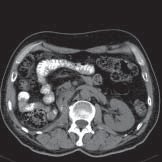

De CT-scanner (afgekort CT) is een apparaat dat door middel van röntgenstralen en een computer afbeeldingen maakt van uw organen, botten en weefsels. Zo’n afbeelding heet een CT-scan. Op een CT-scan is een dwarsdoorsnede van het te onderzoeken orgaan, bot of weefsel te zien. Hiervan kan op een computer achteraf een reconstructie worden gemaakt in een andere richting. Hieronder ziet u enkele voorbeelden van CT-scans.